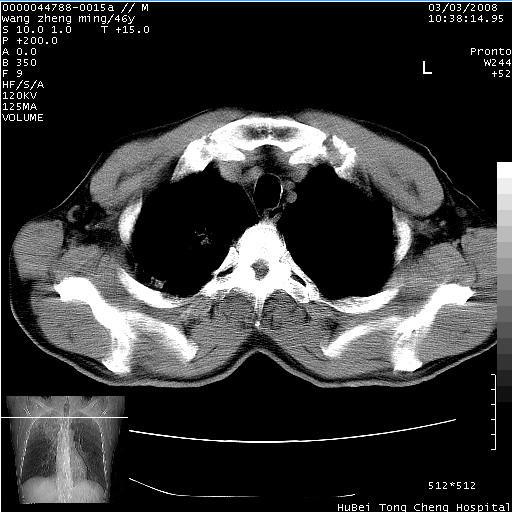

以下是引用卜一在2008-3-22 1:37:00的发言:[br]右肺实质性肿块,边缘不整,明显见毛刺征 分叶征及胸膜凹陷征,右上叶支气管明显变窄,远端散在的片状 斑片状实变影。另:左肺门较大肿块,支气管受累 变窄,远侧见阻塞性肺炎。纵隔内见肿大淋巴结。多考虑:右肺周围性肺癌伴左肺门 纵隔淋巴结转移!